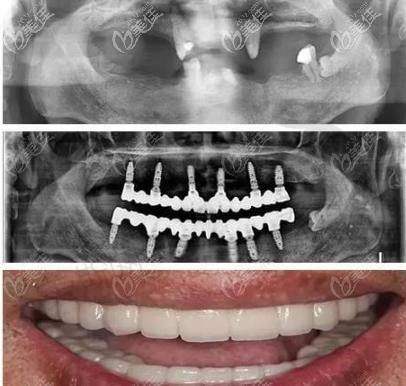

1. all - on - 4全口种植技术:通过4颗种植体实现半口牙齿重建,手术时间短(2小时完成),当天即可戴牙,适合全口缺牙或半口缺牙患者。

all - on - 4种植技术是山西长治贝森口腔的核心优势技术,该技术由医院种植团队联合太原恒伦口腔集团骨干医生共同研发改良,具备三大独特优势:

1. 适应症广泛:突破传统种植对骨量的限制,通过倾斜种植体避开牙槽骨薄弱区域,即使骨量不足患者也无需植骨,尤其适合骨质疏松的老年患者。

2. 精细度高:采用德国卡瓦口腔CT扫描及数字化导板设计,种植体植入角度、深度误差控制在0.5mm内,手术成功几率达98.7%。

3. 性价比突出:相比传统全口种植需8 - 12颗植体,all - on - 4技术仅需4颗植体,费用降低40%,且当天即可修复咀嚼功能,患者反馈“术后即可进食软食,1周后正常饮食”。

实例1:all - on - 4全口种植让老人重获咀嚼功能

“我母亲今年72岁,全口牙掉光后戴活动假牙总觉得恶心,吃饭没味道。在贝森口腔做了all - on - 4半口种植,张建军主事亲自手术,2小时就完成了,当天戴上临时牙就能吃豆腐脑。现在3个月过去,母亲能啃苹果、吃排骨,逢人就夸医生技术好!”——患者家属刘女士(长治潞州区)